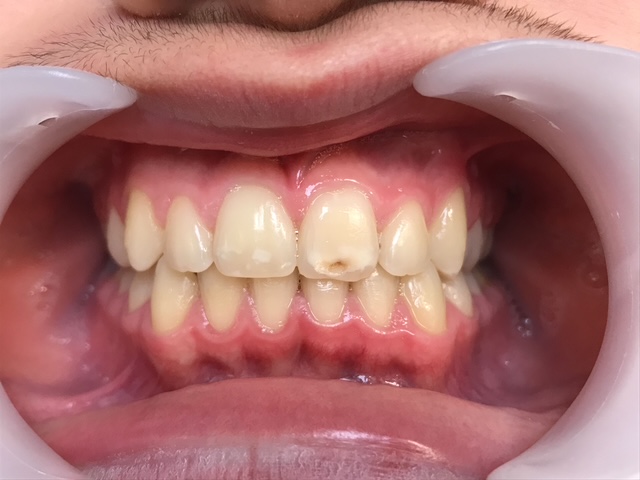

Un cas de recouvrement trop important avec bruxisme sévère :

La photo intermédiaire permet de voir que la situation en denture mixte était bien plus favorable qu’au départ. Quelle dentition aurait eu ce patient si on l’avait traité seulement à 12 ans ? et toutes les tensions dans son corps qui accompagnent ce genre de cas auraient surement perturbé sa croissance générale.

Photos à 6 ans, 9 ans et 15 ans